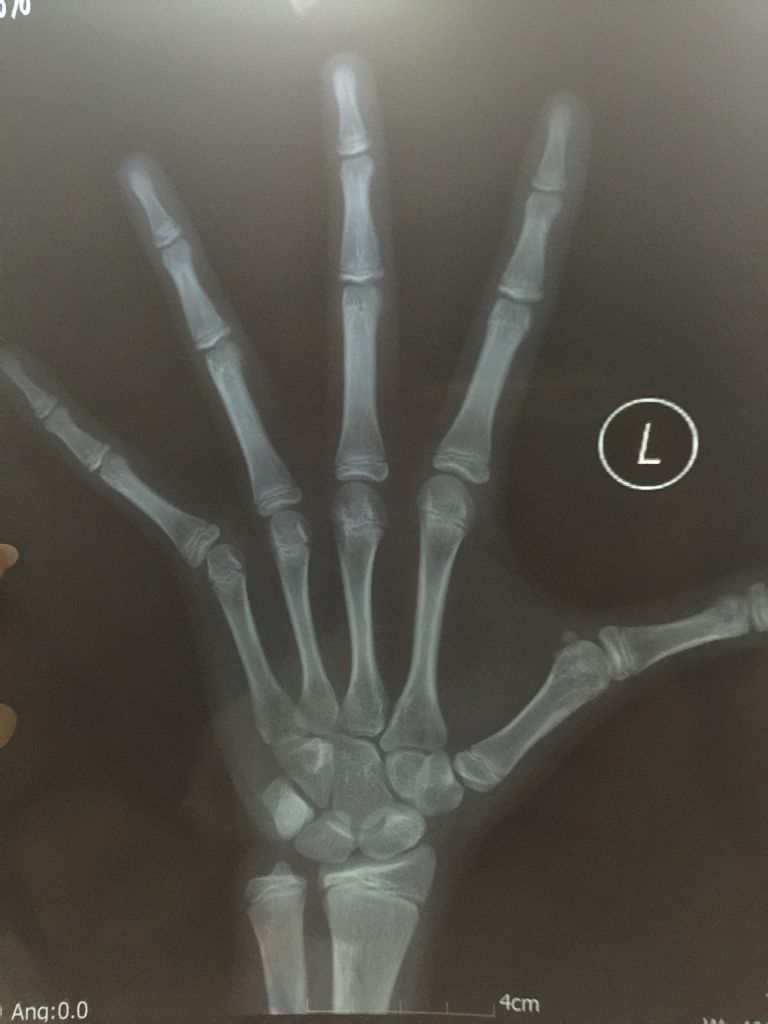

专业骨科医生请进,帮忙看下骨骺是否要闭合了?女孩10.8岁,已来初潮一月,骨龄CHN法测出骨龄已经

专业骨科医生请进,帮忙看下骨骺是否要闭合了?女孩10.8岁,已来初潮一月,骨龄CHN法测出骨龄已经12.6岁了!现在身高147,请帮忙看下不打生长素,让她自然长高,还有多长的时间能长个?